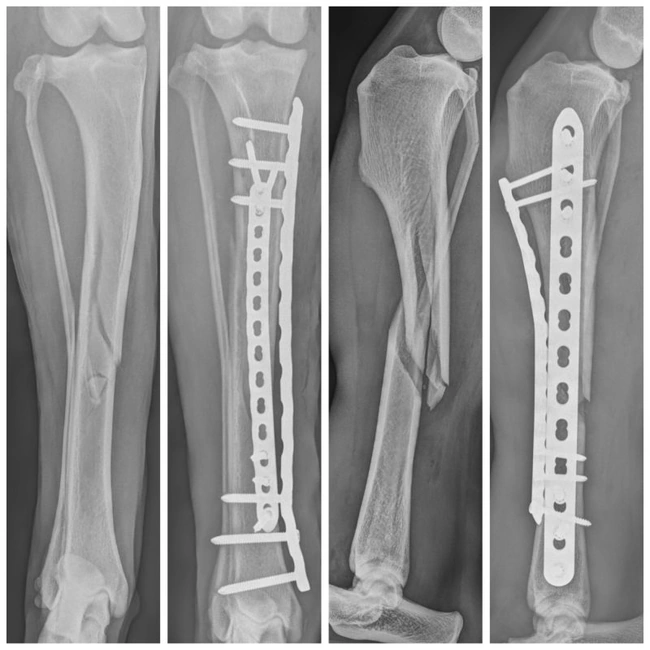

- Traumatología y ortopedia: diagnóstico y cirugía de fracturas, displasia o problemas articulares.